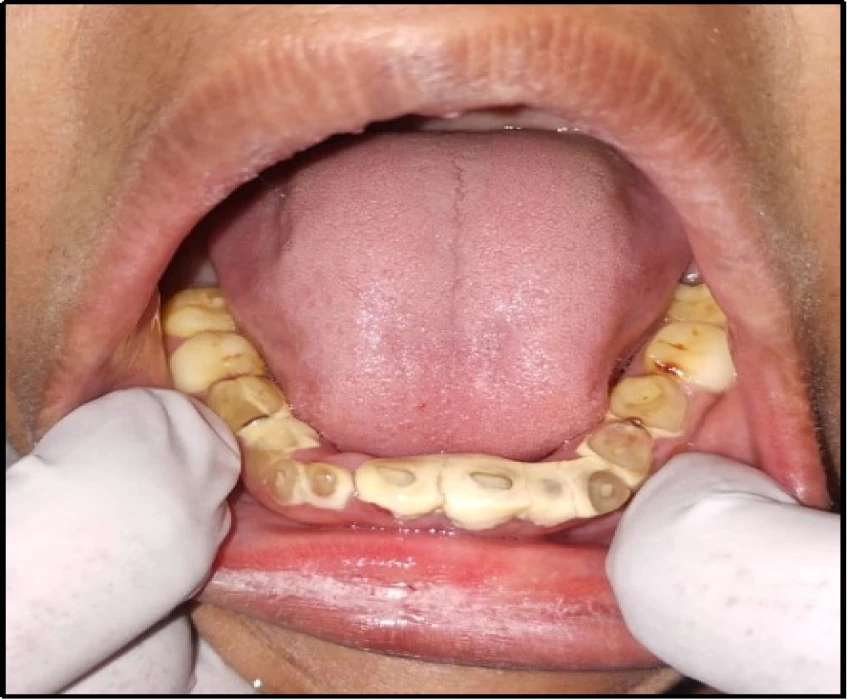

On intra-oral examination generalized loss of cervico-occlusion height and colour of the teeth appeared opalescent and brown in colour.

On the basis of history, clinical examination, and radiographic investigation final diagnosis was given as Amelogenesis imperfecta- Hypoplastic Type.

In patients with hypoplastic amelogenesis imperfecta, the basic alteration centers on inadequate deposition of enamel matrix. In the generalized pattern, pinpoint-to-pinhead–sized pits are scattered across the surface of the teeth and do not correlate with a pattern of environmental damage. The buccal surfaces of the teeth are affected more severely. Both dentitions, or only the primary teeth, may be affected. All of the teeth may be altered, or only scattered teeth may be affected.